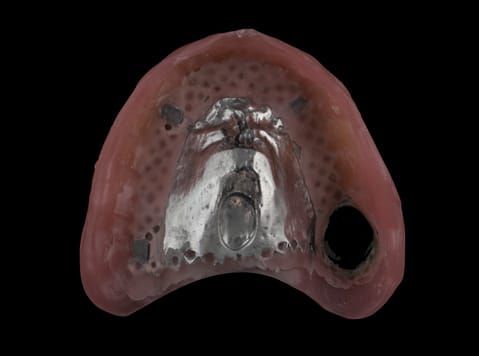

- Cobalt chromium reinforced gasket denture - using a Molloplast B "O" ring to retain and stabilise the denture. This was my professional preference as this was the least invasive and simplest solution to this dental problem. Should the UR7 require removal in the future - an artificial tooth could be added - resulting in a complete denture. The patient would have adapted to the denture fully by this stage and have good neuromuscular control of the prosthesis.

Following consultation and second discussion appointment the patient chose to have option 2 namely, a window denture - maxillary cobalt chromium based partial denture. The clinical situation and treatment process is shown in detail below with photographs. The patient was successfully rehabilitated with this and her quality of life considerably improved. The clinical work was provided by Finlay and the technical work by Rowan.